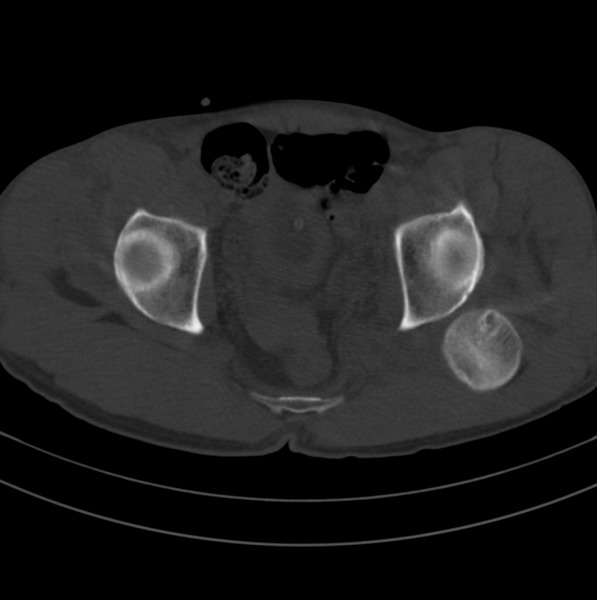

标题: CT18589:股骨头囊状阴影怎么下结论?

男、53

股骨头内的囊状阴影怎么下结论?

1.左髋后脱位。

2.囊状影考虑退变。

髋关节脱位、股骨头疝窝。

左髋关节脱位,其内圆形低密度影,考虑为股骨头疝窝

左侧髋关节后脱位;左侧股骨头疝窝。

左侧髋关节后脱位;左侧股骨头疝窝

一、发病机制

股骨颈疝窝是发生于股骨头基底和股骨颈的一种较少见的良性病变。发病率约在4% 一5% ,好发于中老年人,多无明显症状,常因其他病变检查时偶然发现 。病变多单侧发生,少数为双侧。影像学的正确诊断,可避免不必要的外科手术。

股骨颈疝窝系股骨颈反应区(reaction area)的纤维结缔组织和(或)液体在前部关节囊、髂股韧带及髂腰肌(腱)的机械性压迫下,通过骨皮质疝入松质骨内而形成的窝状骨质缺损 。人体站立或行走时,髋关节囊前方结构处于不断的紧张和松弛交替状态,前部关节囊(尤其是股骨颈轮匝韧带前部环绕区)和相邻的股骨头基底和股骨颈近段前外侧皮质问存在长期的压迫和相互摩擦,使邻近覆盖的滑膜组织可能因受刺激致纤维软骨化生而形成纤维结缔组织和新生软骨,相互摩擦致皮质反应性成骨,后3者成分和其内的液体共同组成了股骨反应区 。

二、影像学表现

x线平片和ct上多表现为位于股骨头基底和股骨颈近段前侧皮质下、股骨颈中轴线外侧的圆形或卵圆形透亮区或软组织密度灶,边界清楚,多伴有薄层硬化缘。病灶最大径线通常<10 mm。病灶或相邻上下层面上相邻皮质大多可见与病灶相连的局限性裂隙样缺损,可作为诊断此病的特异性征象。病灶内通常为纤维结缔组织和(或)液体。内为液体时,病灶呈均匀长t1、长t2信号。纤维结缔组织和液体同时存在时,病灶于t1wi上呈低信号,t2 wi上呈不均匀高信号。